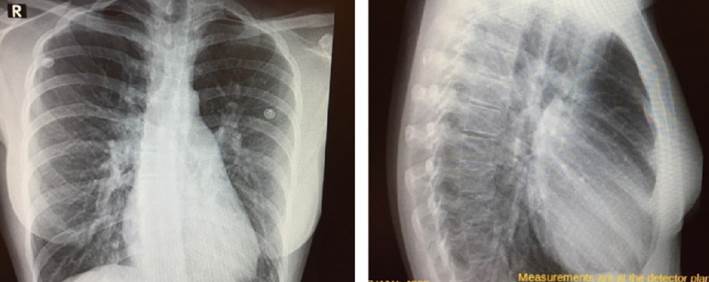

Paciente de sexo femenino, 22 años, sin antecedentes personales a destacar. Consulta en policlínica por cuadro de disnea de esfuerzo (DE) clase funcional II de la New York Heart Association de 6 años de evolución, acompañado de palpitaciones esporádicas. Niega otros elementos patológicos de la esfera cardiovascular. En el examen físico cardiovascular destaca un ritmo regular de 75 ciclos por minuto (cpm), primer ruido normal, desdoblamiento fijo del segundo ruido, soplo sistólico eyectivo a nivel precordial con máxima auscultación en región paraesternal izquierda. Resto del examen físico normal. Electrocardiograma (ECG): ritmo sinusal de 80 cpm que alterna con un ritmo auricular bajo, QRS fino, eje eléctrico medio desviado a derecha (+ 120 grados), bloqueo incompleto de rama derecha (BIRD) (figura 1). En la radiografía de tórax (RxTx) de frente y perfil se observa a nivel de los campos pleuropulmonares una plétora pulmonar y a nivel mediastinal una silueta cardio-aorto-pericárdica aumentada, a expensas de aurícula y ventrículo derecho (VD), con un arco pulmonar prominente (figura 2). El ecocardiograma transesofágico reportó un ventrículo izquierdo de dimensiones normales, con función sistólica conservada, aurícula derecha (AD) levemente dilatada, VD severamente dilatado (diámetro 43 mm) con función sistólica conservada, CIA tipo seno venoso superior de 18 mm de diámetro mayor con pasaje de flujo de izquierda a derecha que asocia retorno anómalo de vena pulmonar superior derecha (VPSD) a la VCS, 10 mm por encima de su desembocadura en la aurícula derecha, con una relación gasto cardíaco-pulmonar/gasto cardíaco-sistémico de 2,8 (Qp/Qs). Hipertensión arterial pulmonar moderada (presión sistólica de la arteria pulmonar 48 mmHg). Dado este último hallazgo, se solicita cateterismo cardíaco derecho que descarta hipertensión arterial pulmonar, informa CIA tipo seno venoso superior, con resistencias arteriales pulmonares (RVP) y sistémicas (RVS) normales con Qp/Qs de 3,13. Se realiza angiotomografía de tórax que evidencia retorno anómalo de VPSD que desemboca en VCS a unos 20 mm por encima de la AD (figura 3).

En esta patología, el shunt está dado tanto por el pasaje de sangre desde el retorno pulmonar anómalo a las cavidades derechas, así como a través de la propia CIA. La magnitud del shunt a través de esta última depende del gradiente de presión entre AI y AD, compliance de ambos ventrículos, relación entre RVP y RVS y la presencia de otras cardiopatías asociadas (valvulopatía mitral-aórtica, cardiopatía isquémica, hipertensión arterial). En general, los pacientes cursan asintomáticos hasta la edad adulta; el 50% presentará síntomas a los 20 años, debido principalmente por disnea de esfuerzo y palpitaciones, siendo menos frecuente la falla cardíaca derecha y la infección pulmonar(1). Con respecto al examen físico, se destaca a nivel cardiovascular un soplo sistólico eyectivo en foco pulmonar debido a hiperflujo y un desdoblamiento fijo del segundo ruido por aumento del tiempo diastólico del VD. Por su parte, los hallazgos electrocardiográficos son concordantes con la presencia del defecto interauricular (ritmo auricular bajo, desviación a derecha del EEM y BIRD). A nivel de la RxTx encontramos claros elementos de remodelado de cavidades derechas, así como signos de hiperflujo pulmonar. El ecocardiograma transtorácico es la herramienta fundamental para definir el diagnóstico y la estrategia terapéutica, permite valorar, entre otros, el tipo, el tamaño, la forma y la relación del defecto con estructuras adyacentes. El hallazgo de un VD severamente dilatado, en ausencia de valvulopatías significativas y patología pulmonar preexistente nos debe alertar de la presencia de un posible shunt interauricular. En este caso, el ecocardiograma transesofágico permitió identificar una CIA tipo seno venoso superior y la presencia de retorno anómalo de vena pulmonar superior derecha desembocando en la VCS. La valoración completa del retorno venoso anómalo debe complementarse con otros estudios de imagen como la angiotomografía de tórax con contraste o la resonancia magnética, donde es fundamental definir, entre otros valores, la distancia entre su desembocadura en la VCS y la AD, para planificar una correcta estrategia terapéutica(1).